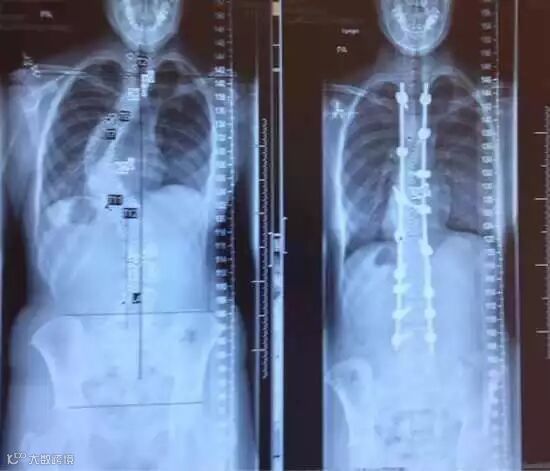

脊柱侧弯的X光照片(治疗前/治疗后)